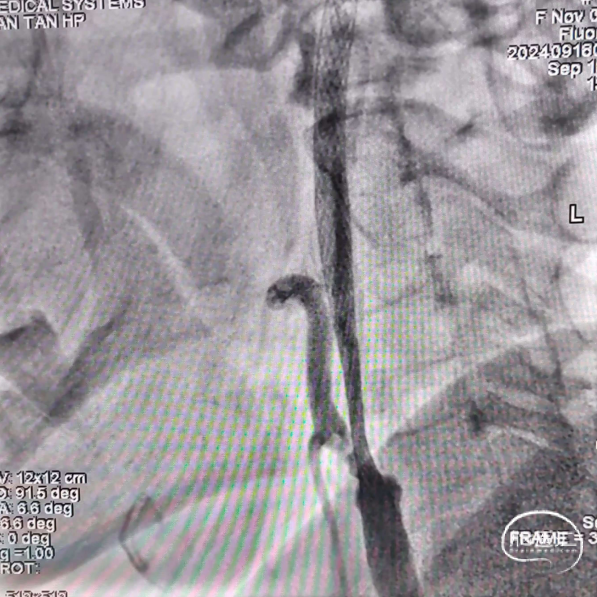

术前造影

RVA正位

RVA侧位

LVA正位

LVA侧位

LCA正位

LCA侧位

沿泥鳅导丝送入5F多功能携带8F导引导管至左侧颈内动脉C1段闭塞处,撤出泥鳅导丝及多功能导管,进行造影。

在路径图下,沿导引导管同轴技术送入微导丝(Command ES 0.014inch 300cm)带Rebar 18微导管至左侧颈内动脉C1段闭塞处,应用微导丝多次尝试成功通过闭塞处,撤出Command交换为Transend微导丝送至大脑中动脉远端。

微导丝、微导管到位后造影,证实微导管位于真腔内。